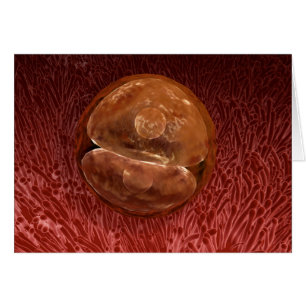

Développement Du Foetus À 9 Semaines

Prix de vente 5.44 CHF. Prix Initial 6.04 CHF.